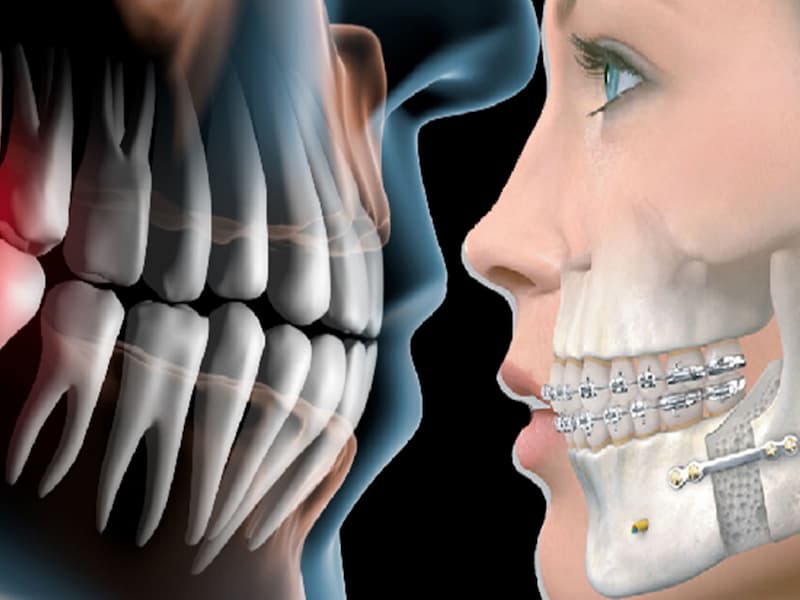

در واقع با استفاده از این روش می توان دندان مصنوعی قرار داد که معمولا با جراحی کردن نیز همراه است.

باید در هنگام خرید به ایمپلنت مورد نظر به خوبی دقت کنید تا از درجه کیفیت بالایی برخوردار، عملکرد مناسبی داشته و همچنین بتواند به راحتی در داخل فک جای بگیرد.